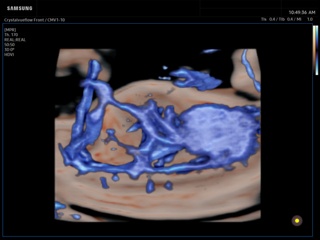

In the section "Оbsterics" of atlas the results of ultrasonic examinations of pregnant women with different durations of gestation are represented. Here you can see images of internally organs, cerebrum, cordis and the sex of the fetus, the sonograms of multiple pregnancy, the blood flow in placenta and umbilical cord, defects of fetal`s development, etc.